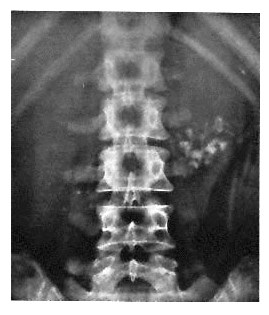

23F progressive low back pain & stiffness over years, worsened recently. pain relieved with activity and ibuprofen. on exam, reduced forward flexion of lumbar spine & tenderness over lumbosacral area.

what does the xray show? what is most likely to diagnose this? what is the likely dx?

bamboo spine (fusion of the vertebral bodies & discs)

x-ray of sacroiliac joints

ankylosing spondylitis